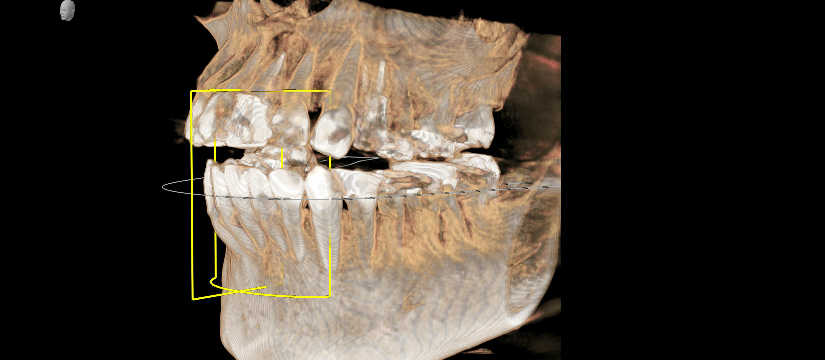

気道解析 airway

当クリニックのCTには気道解析ソフト「SICAT AIR」がインストールされております。気道の空間容積を分析するためのものです。一見すると、歯科とは無関係に思われるかもしれませんが、、、

欧米ではすでに健康寿命を損なう疾患として睡眠時無呼吸症候は認知されており、睡眠時無呼吸症の9年生存率は62%という報告もあります。我々歯科医が日常的に行う矯正や全顎的な咬合治療においては、気道を閉塞させてしまうことも考えられ、それらを考慮した治療も必要になってきます。全顎的な治療介入を行い、気道を閉塞させてしまうリスクがある場合は、歯科治療に伴う健康寿命の損失を予防するためにも気道の状態の確認することが重要になってきます。まだ日本ではその認知と治療が浸透しておりませんが、近い将来、気道を確認することも歯科医に求められてくると思います。